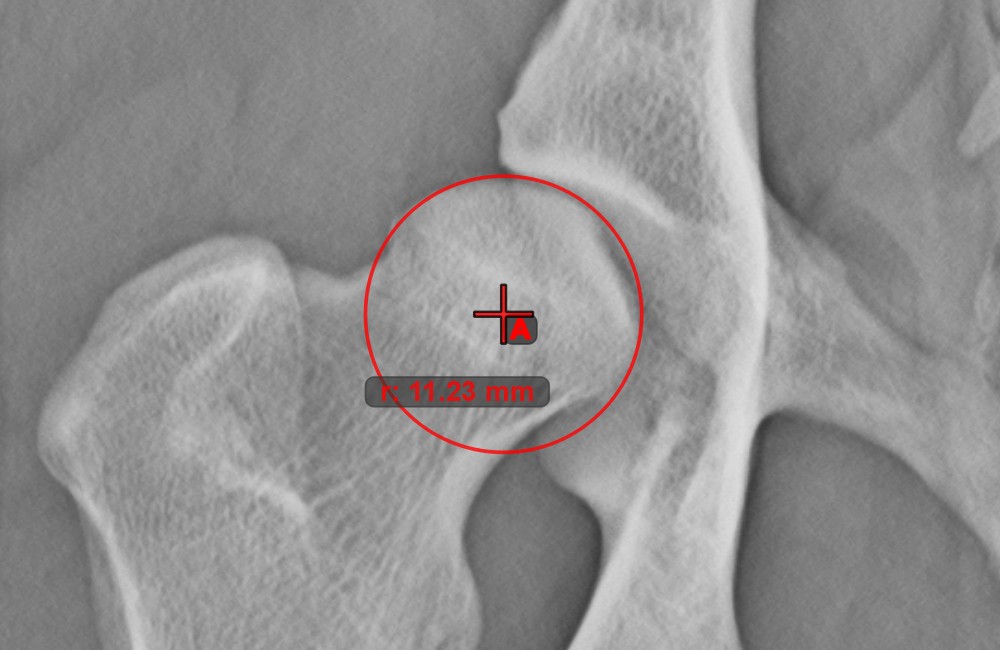

Circle from 3 Points¶

The Circle from 3 Points tool is a simple and effective way to create a circle from just three points.

Start by selecting the tool from the left toolbar and assign it to one of the available mouse buttons. Place the three points of the circle, or select the points from ones available on the scene. The circle will be automatically created based on the position of the three points. The origo of the circle will always be marked with O. The radius of the circle is automatically calculated.

Modify the position of the three points to change the radius of the circle by using the Select/Move Item tool.

Circle with Defined Radius¶

Draw a circle with fixed radius by using the Circle with Defined Radius tool. Only the position of the circle on the scene can be modified later.

Select the tool from the left toolbar and assign it to one of the available mouse buttons. Place the origo of the new circle on the scene or select an already existing point. Specify the desired radius of the circle and press OK

to complete the measurement.